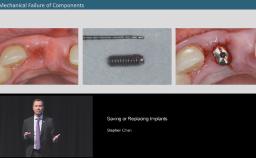

- Prosthetic considerations regarding the type of attachment, type of occlusion, the value of wax-ups as well as the differences between internal and external hex connections for implant bridges.

- Surgical considerations regarding the type of bone augmentation procedure and the timing of implant placement.